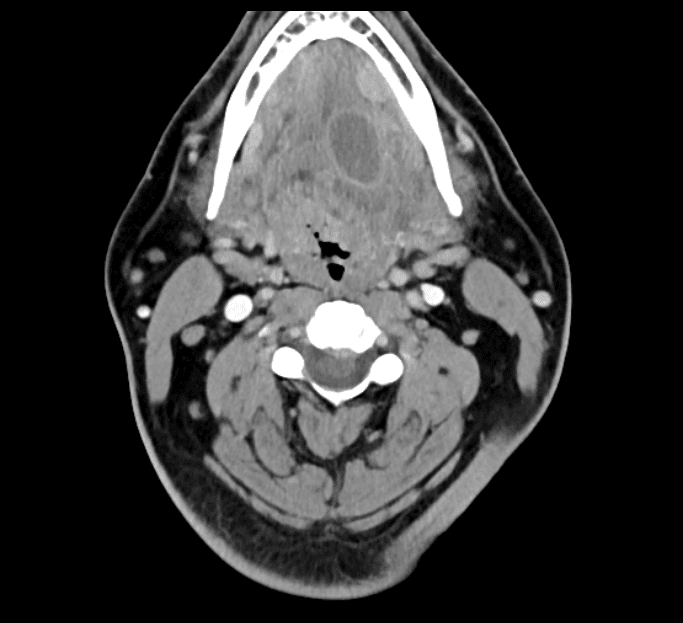

- Left Glossotonsillar Sulcus SCCA CT

- Right Glossotonsillar Sulcus Ca Classic

- Floor of Mouth SCCA Carcinoma

- Left Tonsilar Cancer

- SCC of the Tonsil

- Right Tongue Base SCCA